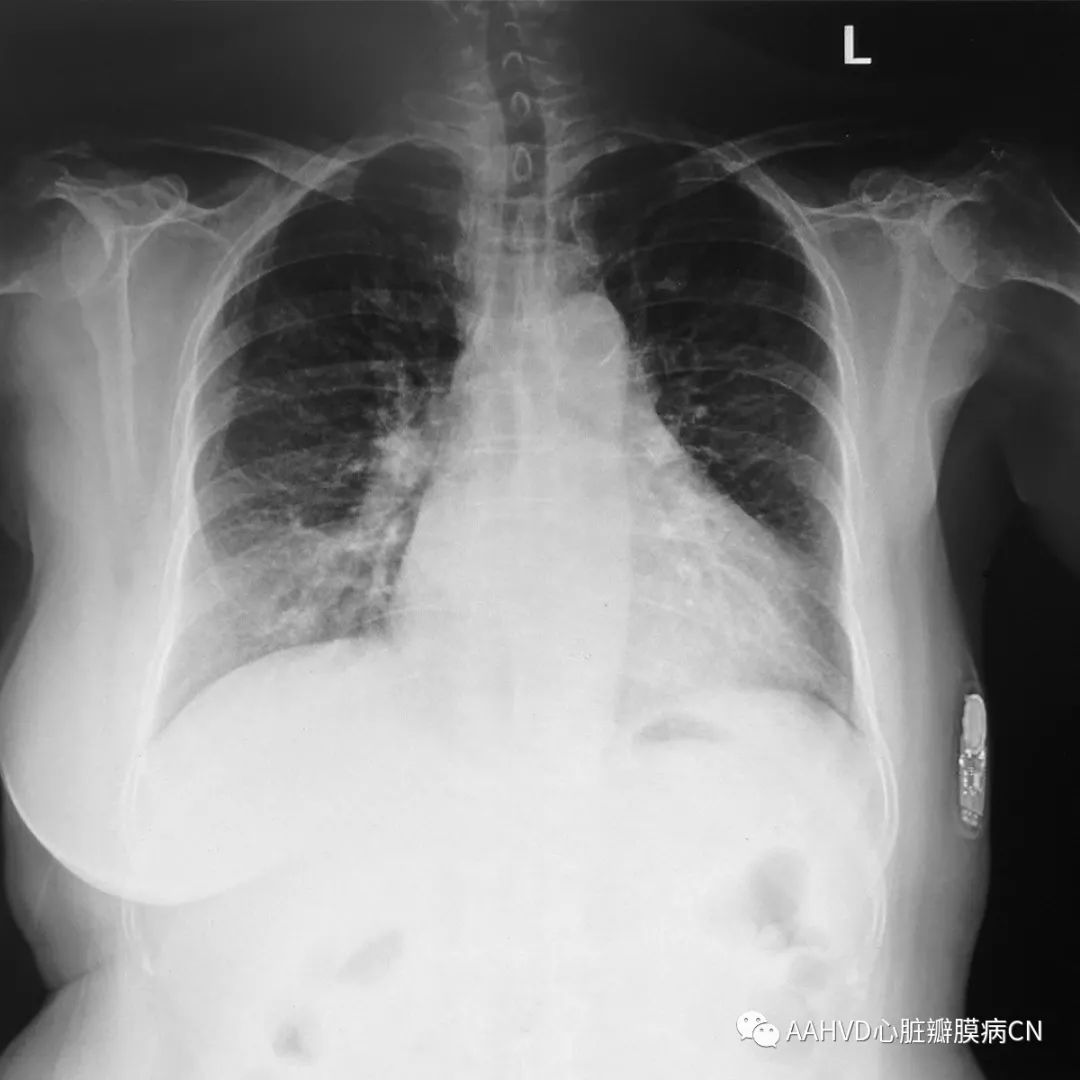

术前胸片

640_2